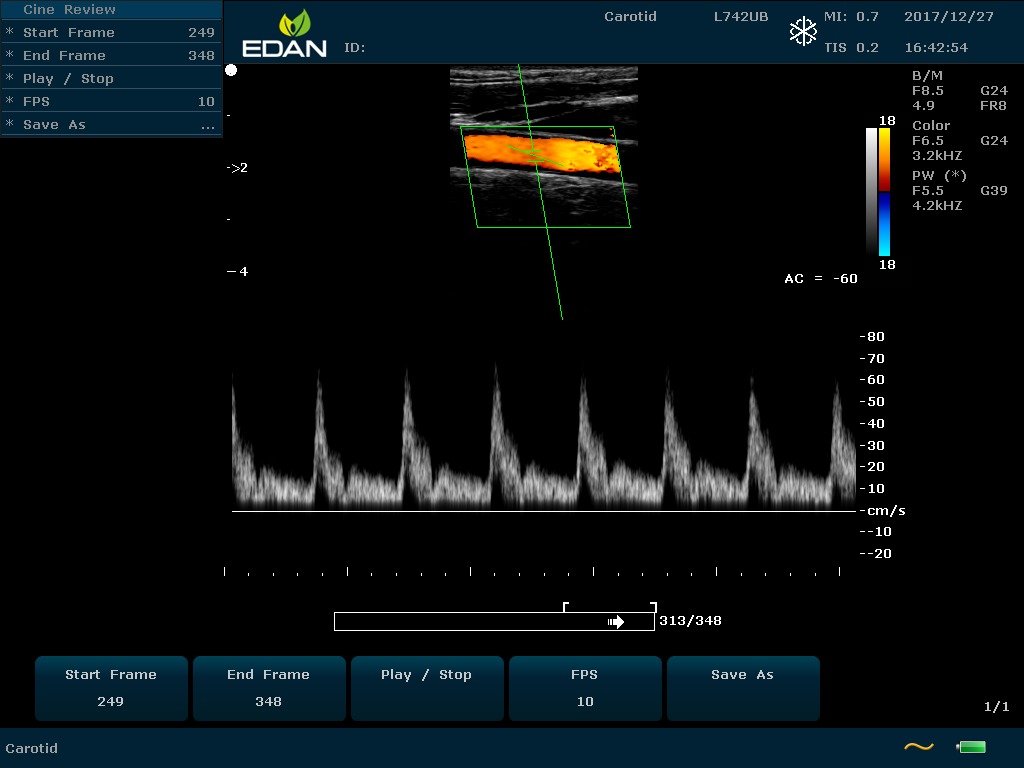

Передовые технологии позволяют повысить качество визуализации в несколько раз. УЗИ-аппарат U60 Edan отличается возможностью быстрой настройки визуализации. Специальные функции позволяют моментально отображать данные за счет быстрой оптимизации параметров. Режимы визуализации: B-mode, M-mode, Color Doppler, Power Doppler Imaging, Pulsed Wave Doppler, Continuous Doppler.

• Цветовое Допплеровское картирование

• Импульсная Допплерография

• Непрерывноволновая Допплерография

• Спектральный Допплер с высокой частотой повторения импульсов

• Направленная энергетическая Допплерография